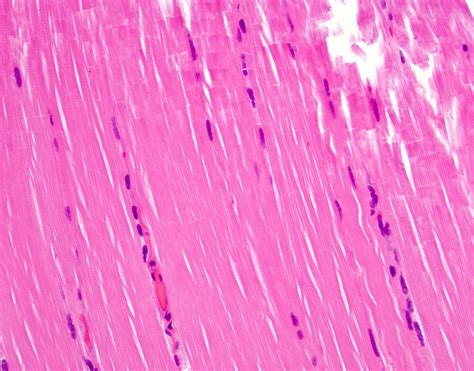

To visualize these structures clearly under a light microscope, histologists employ specific staining methods. The standard Hematoxylin and Eosin (H&E) stain is the most common, where Hematoxylin stains the nuclei blue/purple, and Eosin stains the sarcoplasm and connective tissues pink/red. For more advanced analysis, special stains like Masson’s Trichrome are used to differentiate collagen fibers (blue) from the muscle tissue (red), which is particularly useful for identifying fibrosis or connective tissue damage.

💡 Note: When viewing histology slides, always pay attention to the cross-sectional view versus the longitudinal view; cross-sections reveal the characteristic "polygonal" shape of fibers and the peripheral location of the nuclei.